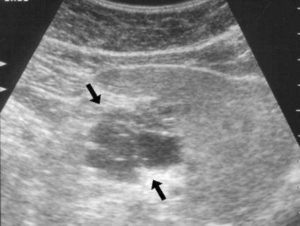

На УЗИ, поджелудочная железа должна выглядеть как однородная субстанция. Однако, при наличии патологий, ее размеры могут быть изменены, а плотность (эхоплотность) может отклоняться от нормы в любую сторону (повышенная или пониженная). Также могут быть видны очаги заболеваний и неоднородность структуры. Хотя УЗИ может показать эти изменения, определить конкретное заболевание возможно только после проведения соответствующего обследования.

Диффузные изменения поджелудочной железы не являются отдельным диагнозом, а являются общим термином, который указывает на наличие патологии в органе и был обнаружен в процессе ультразвуковой диагностики. Термин «диффузный» означает, что заболевание равномерно распространяется по всему органу, а не имеет очаговых нарушений.

Какие виды диффузных изменений выявляют на УЗИ?

Изменения поджелудочной железы могут проявляться различными способами:

- В случае острого воспаления, вызванного нарушением выведения пищеварительных ферментов, эхоплотность уменьшается, эхоструктура становится неоднородной, но размеры железы остаются в пределах нормы. Это может привести к самоперевариванию органа и возникновению отечности.

- При хроническом панкреатите эхоплотность поджелудочной железы снижается, она становится менее плотной, но размеры органа не изменяются. Эти эхо-симптомы свидетельствуют о нарушении обменных процессов в железе и возможном закручивании протока отхода соков.

- Повышенная эхогенность железы, сопровождающаяся увеличением эхоплотности, но без изменения размеров, может указывать на липоматоз — замещение стенок поджелудочной железы жировой тканью.

- Диффузные изменения паренхимы поджелудочной железы, сопровождающиеся изменением плотности эхоструктуры, характерны для сахарного диабета.

- Повышенная эхогенность (гиперэхогенность) и уплотнение (повышение эхоплотности) поджелудочной железы, при сохранении нормальных размеров или незначительном уменьшении, могут свидетельствовать о наличии фиброза, вызванного воспалением или дефектами процесса прохождения пищи через ЖКТ.

- Диффузорные дистрофические изменения, обнаруженные при эхо-осмотре, являются необратимыми и прогрессирующими, но не имеют конкретных симптомов.

- Гиперэхогенность железы может быть связана с наличием псевдокист или абсцессов.

- Неоднородность диффузии эхо-структуры железы указывает на смешивание участков.

Для анализа таких изменений важно провести полное исследование, включающее результаты анализов крови, мочи и других методов диагностики, чтобы поставить точный диагноз.